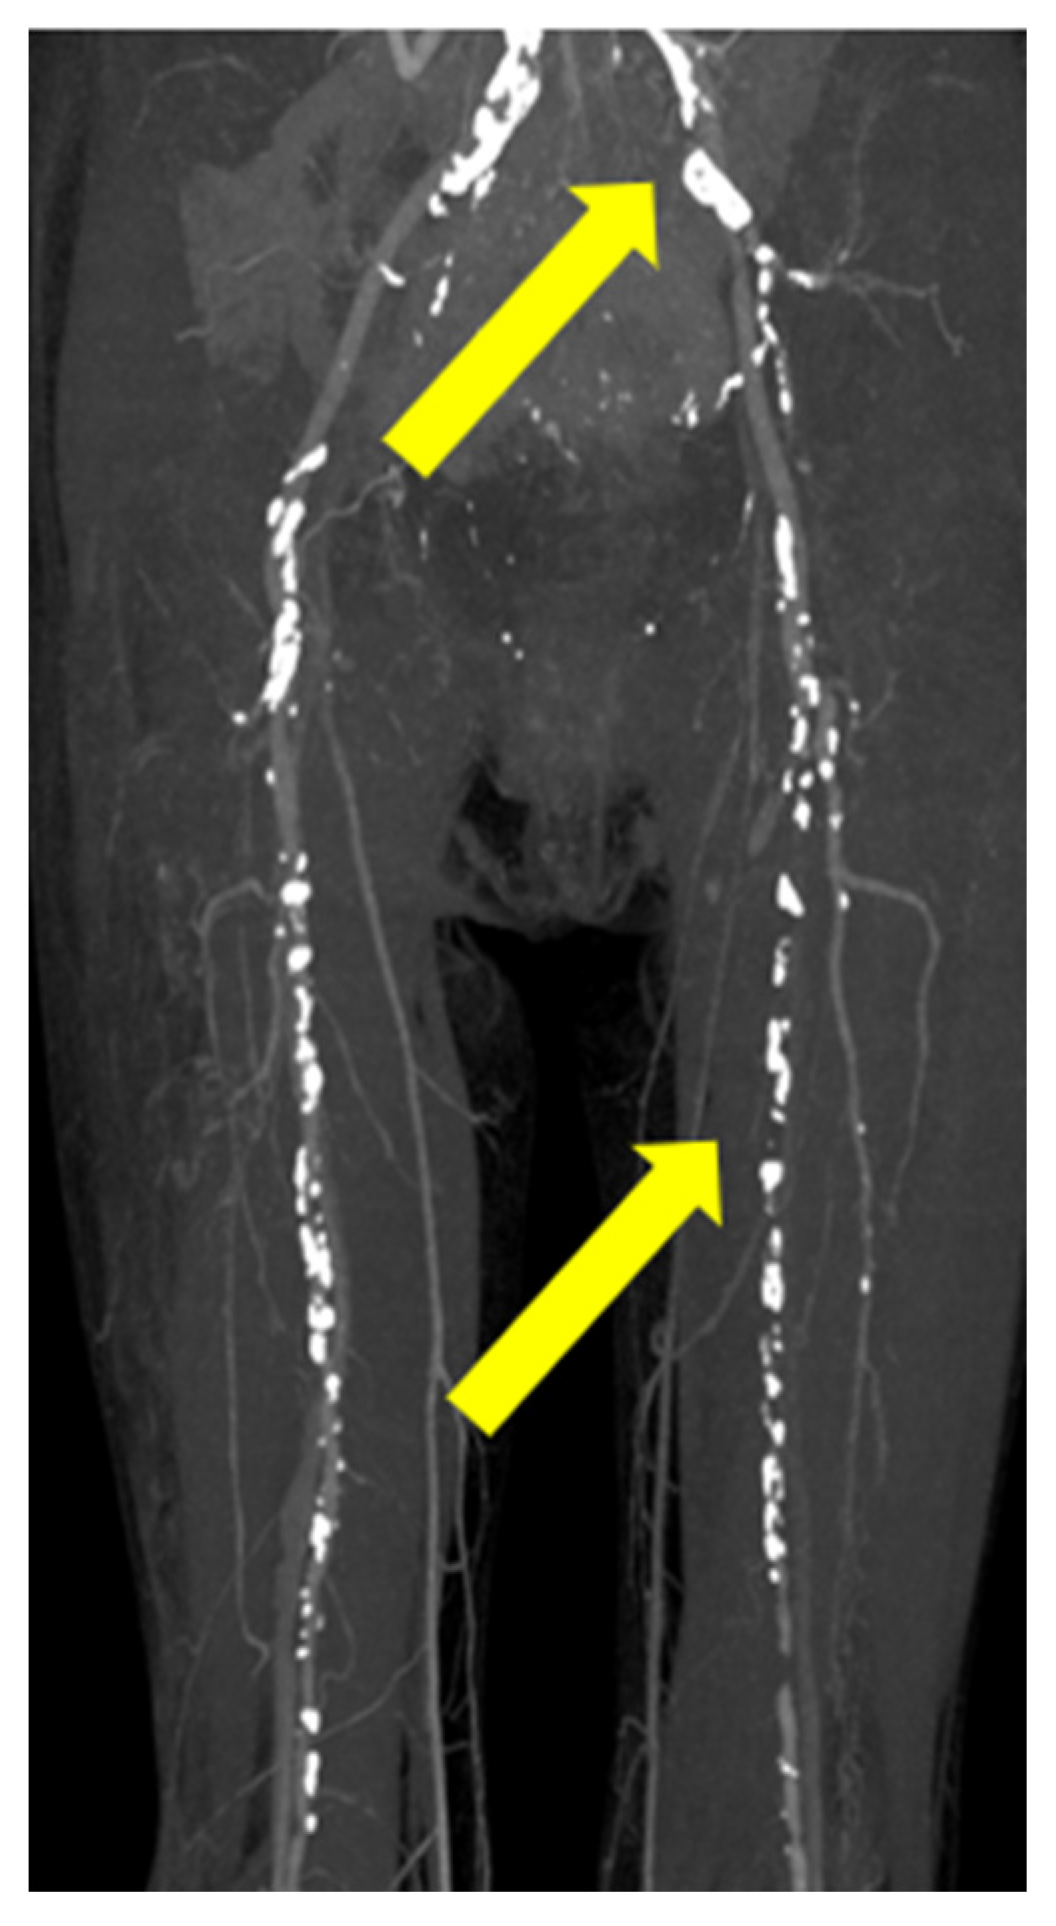

An additional biopsy of the lower limbs was also suggested; however, she refused this due to severe pain in the lower limbs. Eliminating degenerated fibers, cutaneous symptoms, and the occurrence period led to the diagnosis of ARPD [1,2,3]. The perforating dermatosis was classified as severe (16.4) [1,2,3]. Laboratory examination revealed elevated HbA1c (10.8%) and glucose (382 mg/dL) and normal creatinine level (0.75 mg/dL). Contrast computed tomography revealed arterial narrowing and ischemia of the left common iliac artery (CIA) and superficial femoral artery (SFA), indicating PAD (Figure 3).

Figure 3.

Contrast computed tomography revealed arterial narrowing and ischemia of the left common iliac artery and superficial femoral artery in the left lower limb (yellow arrow).